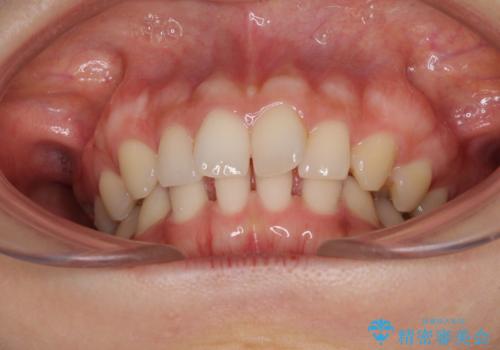

隙間だらけの歯列をきれいに インビザライン矯正とセラミック補綴治療

- 前歯の隙間と奥歯の目立つ銀歯を気にして来院された患者様です。

インビザラインにより下顎前歯の隙間を閉じるとともに、奥歯の咬み合わせを改善させることとしました。

矯正治療後には、銀歯のクラウンをセラミッククラウンへ替える補綴治療を行うこととしました。

左右奥歯の咬み合わせを変更させる必要があったため、治療期間は長くなることが予想されました。

1日22時間以上の装着時間をしっかりと守ってくださったので、順調に治療を進めることができました。